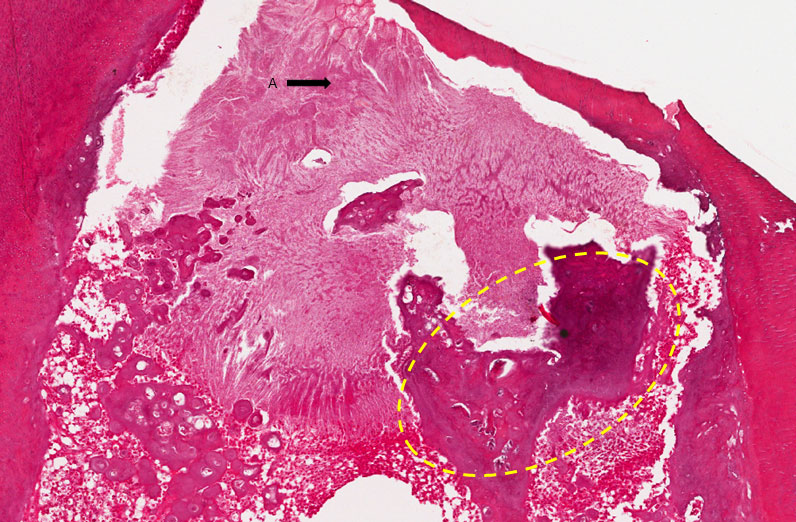

Corte histológico de dente decíduo, mostrando câmara pulpar aberta e recoberta parcialmente por material restaurador (capeamento) (Seta A). Nota-se pequena área de exposição pulpar. Abaixo do material de capeamento, observa-se formação de dentina terciária (osteodentina) (tracejado amarelo) e piócitos (supuração) (asteriscos amarelos) o qual se concentra na área mais superficial. No restante da polpa, observa-se intenso infiltrado inflamatório com predomínio de macrófagos espumosos. Na dentina da porção radicular, pode ser identificada reabsorção interna evidenciada pela ausência da camada de odontoblastos e de pré-dentina associada a presença de células clásticas na interface dentina-polpa, sendo estas as responsáveis pela reabsorção da dentina. Observamos também áreas de reabsorção externa e reabsorção externa compensada.

Observar a cavidade aberta (área de ulceração) material restaurador, formação de dentina terciária, área de supuração e intenso infiltrado inflamatório com predomínio de macrófagos e linfócitos. Em algumas áreas observa-se reabsorção da raiz com presença de clastos (asteriscos verdes) em contato com a dentina radicular (lacunas de Howship – setas pretas) tecido pulpar inflamado.

Obs: Dependendo do plano de corte, o diagnóstico pode variar entre as lâminas. Se a polpa estiver aberta, definimos o diagnóstico como pulpilte ulcerada (ulcerativa). Se houver material recobrindo a polpa, determinando coleção (acúmulo de pus) na câmara pulpar, o diagnóstico a ser dado é pulpite abscedada. Na lâmina escaneada temos uma pulpite aberta – ulcerada.

Pulpite Ulcerada e Reabsorção Interna e Externa